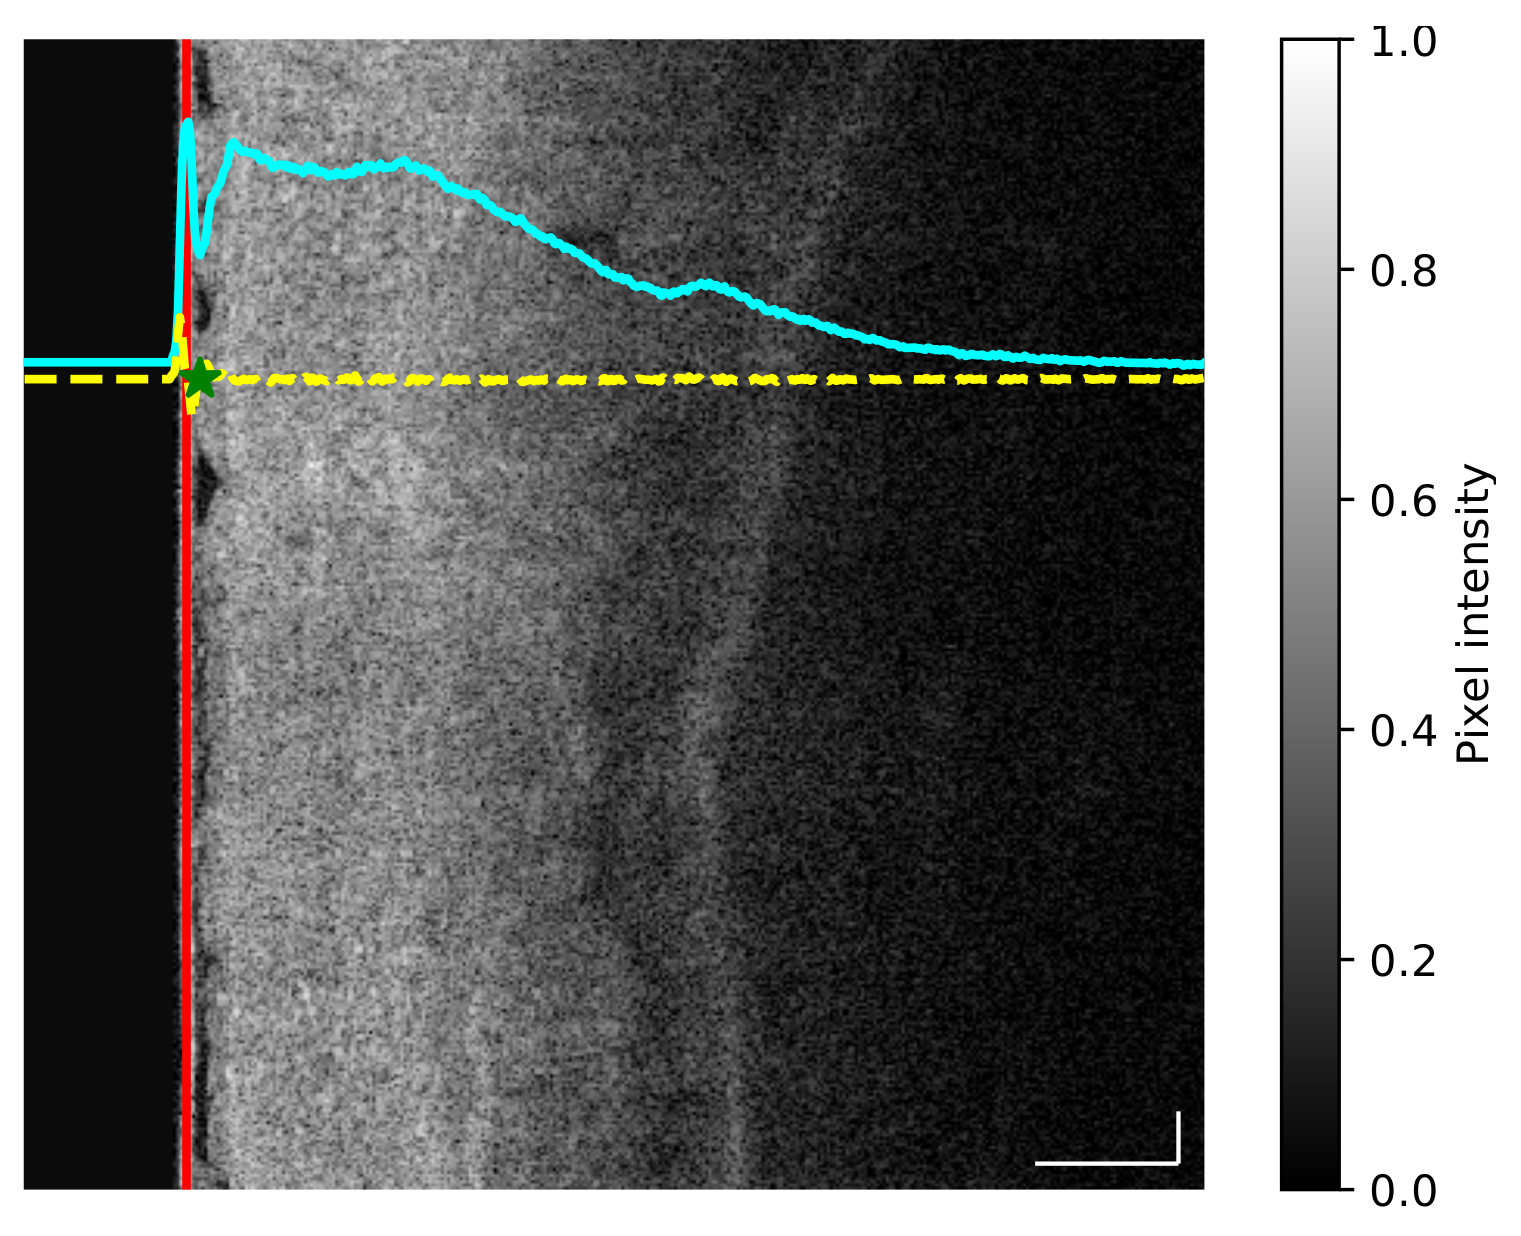

- For each image the average intensity curve was computed along the vertical dimension, thus allowing us to obtain the profile of changing intensity (Figure 1, cyan curve).

- The first derivative of the average intensity curve was computed to obtain a quantitative measurement of slope differences (Figure 1, yellow curve).

- Given the first derivative, the balloon end location was defined as the local maximum value found after the minimum point of the first derivative (Figure 1, green star).